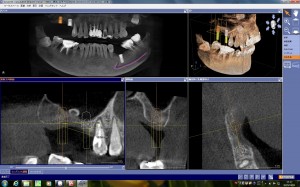

上顎4番部位へセレックガイドでガイデッドサージェリー

上顎の第1小臼歯部へのインプラント埋入をセレックガイドを用いてガイデッドサージェリーで行いました。

使用したインプラントシステムはストローマンですが、シロナのCTとギャラクシスソフトでプランニングをして、院内設置のセレックのミリングマシー…